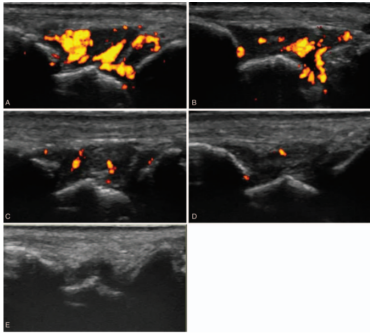

治疗后患者关节疼痛、肿胀、压痛、滑膜增生和超声多普勒信号均明显改善,见表1和图1和图2。结果说明超声引导下关节内注射曲安奈德治疗RA难治性小关节炎有效。

图2 患者44岁,男性,病程2年。用甲氨蝶呤和伊曲肽治疗后RA症状减轻,但是右腕关节仍有肿胀和疼痛。(A)右腕背侧纵视图:3级滑膜增生和血流信号;(B-D)关节内注射曲安奈德后24小时、1周和4周的血流信号;(E)治疗12周后滑膜增生及血流信号,滑膜增生呈衰减(2级),未见血流信号。